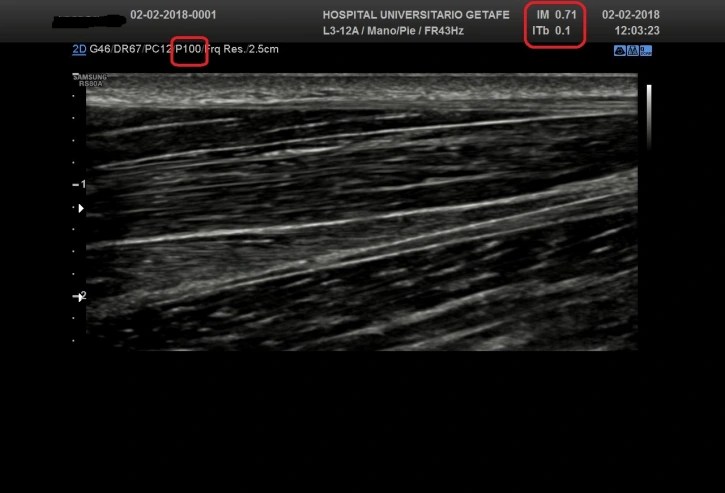

Como puedes ver, regulando la potencia de transmisión (P) bajamos significativamente los ODS. Ves que a valores de la mitad de la potencia máxima, y según que estructura, la imagen no cambia y los ODS sí lo hacen, significativamente.

- Índices de Seguridad: Incluyen índices como el Índice Térmico (TI) y el Índice Mecánico (MI), que ayudan a estimar los riesgos potenciales asociados con el calentamiento de los tejidos y los efectos mecánicos.

En el contexto de las exploraciones ultrasónicas, los valores más importantes para garantizar la seguridad y eficacia del procedimiento se centran en los índices que miden los posibles efectos térmicos y mecánicos del ultrasonido en los tejidos. Estos índices son cruciales tanto para los profesionales que realizan los ultrasonidos como para los fabricantes de equipos de ultrasonido. Los dos índices más relevantes son el Índice Térmico (TI) y el Índice Mecánico (MI).

- El TI es una estimación del potencial de aumento de temperatura en los tejidos debido a la energía ultrasónica.

- Los valores de TI varían según la aplicación del ultrasonido, pero generalmente, un TI por debajo de 1 es considerado seguro. Sin embargo, en aplicaciones sensibles como la ecografía fetal, los profesionales suelen esforzarse por mantener el TI lo más bajo posible, especialmente durante el primer trimestre del embarazo.

- El MI mide el riesgo de efectos mecánicos no térmicos (como la cavitación) que podrían ser causados por el ultrasonido en los tejidos blandos y los fluidos.

- Un MI inferior a 0.3 es generalmente aceptado como seguro en la mayoría de las aplicaciones diagnósticas. Para aplicaciones sensibles, como la ecografía oftálmica, se recomienda un MI aún más bajo.